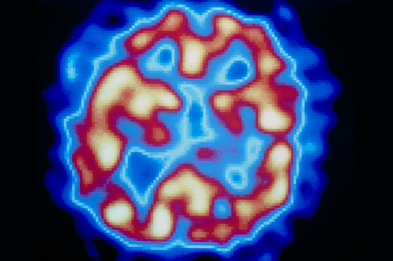

Bipolar Disorder Hallucinations

Images of Bipolar Disorder Hallucinations